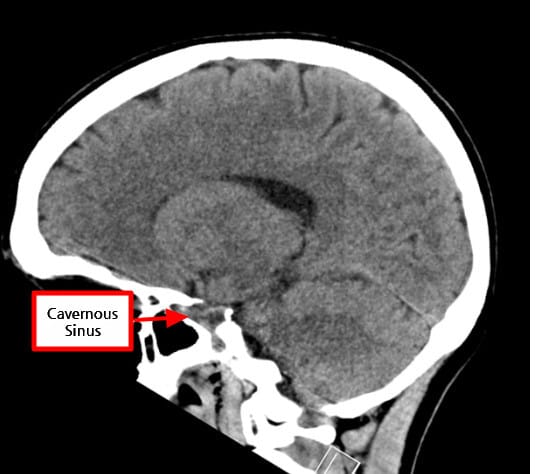

Cavernous Sinus

Cavernous sinus는 접형골(sphenoid bone) 옆쪽에 위치한 정맥혈이 흐르는 공간으로, Dura mater 사이에 존재하는 큰 정맥굴입니다.

- Axial view에서 뇌하수체(sella turcica) 양 옆으로 대칭적으로 보입니다